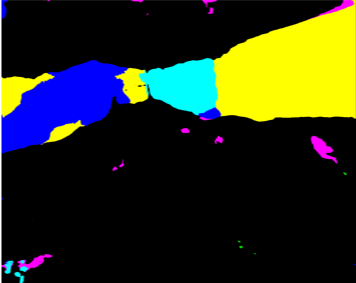

Our challenge was made up of 3 sub-problems. The first was binary instrument segmentation, where each frame was separated into da Vinci Xi instruments and a background class, which contained an ultrasound probe, surgical clips and porcine tissues. The second task was instrument part segmentation, where we scored the participants on whether they could correctly segment each articulating part of the instrument (see Fig. 3). Our final task was to segment and classify the instruments (see Fig. 4).

We provided the first 225 frames of 8 sequences as training data and kept the last 75 frames of those 8 sequences as test data. 2 of the full 300 frame sequences were kept as test sequences. Test labels were kept hidden from the participants. Our datasets contain 7 different robotic surgical instruments. The Large Needle Driver, Prograsp Forceps, Monopolar Curved Scissors, Cadiere Forceps, Bipolar Forceps, Vessel Sealer and additionally a drop-in ultrasound probe, which is typically held in the jaws of the Prograsp Forceps instrument. Samples from the training datasets are depicted in Fig. 2 and examples of the different instrument types are shown in Figure 3 and 4.

IV-D Type Segmentation